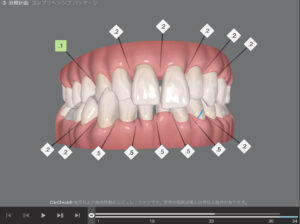

🔶初診時🔶

正面

反対の噛み合わせ 通称 受け口

歯並びガタガタの そうせい を

気にしてマウスピース矯正を希望され来院

🔶アフター🔶